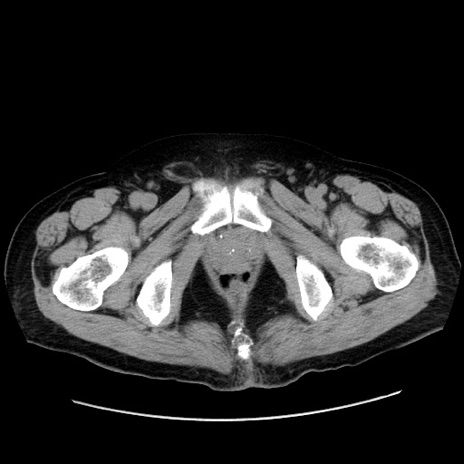

症例30(横断像)

【症例】80歳代男性

【主訴】臍周囲痛

【現病歴】約6時間前から臍下部痛が出現。次第に腹部膨隆・背部痛も生じてきたため来院。背部痛の場所は変化しない。

【身体所見】意識清明、BT 36.3℃、BP  131/87mmHg、P 87bpm、SpO2 100%(RA)、臍周囲自発痛・圧痛あり、反跳痛なし、自発痛部位に一致して板状硬あり、腹部膨隆、腸雑音減弱、CVA tenderness両側陰性。

【データ】WBC 19600、CRP 0.33